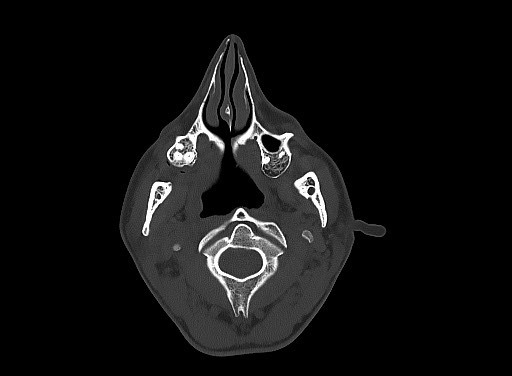

CT

High-density bone deposition within the membranous labyrinth:

mild disease: hazy increase in density within fluid spaces of the membranous labyrinth

moderate disease: focal areas of bony encroachment on fluid spaces of the membranous labyrinth

severe disease: membranous labyrinth completely obliterated by bone replacing fluid spaces

The term otosclerosis is somewhat of a misnomer. Much of the clinical course is characterised by lucent rather than sclerotic bony changes and hence it is more appropriately known as otospongiosis which is a term preferred by many head and neck radiologists.